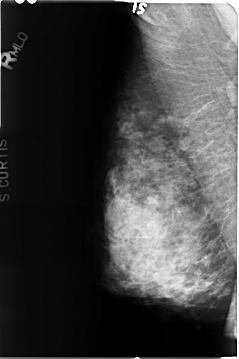

B_3495_1.RIGHT_MLO

RIGHT_CC LINES 4752 PIXELS_PER_LINE 3184 BITS_PER_PIXEL 12 RESOLUTION 50 NON_OVERLAY

RIGHT_MLO LINES 4664 PIXELS_PER_LINE 3096 BITS_PER_PIXEL 12 RESOLUTION 50 NON_OVERLAY